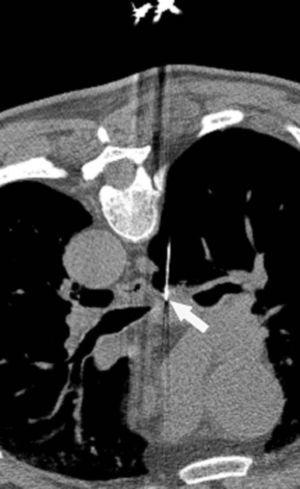

Pese a las conocidas limitaciones de la TC, ésta continúa siendo la técnica de elección en la estadificación del tumor en los pacientes con CPNM; su sensibilidad y especificidad en la determinación de la infiltración de pared oscilan entre el 38 y el 87% y del 40 al 90%, respectivamente, según las series. El desarrollo de nuevos equipos de TC helicoidal y principalmente las TC multidetectoras (TCMD) proporcionan unas imágenes 2D de mayor resolución con la posibilidad de hacer reconstrucciones multiplanares (MPR) en distintos planos del espacio e incluso 3D con la consiguiente mejora de la valoración del tumor, su extensión e infiltración de estructuras vecinas5 (fig. 4). Así, con la TCMD se puede poner de manifiesto con mayor fiabilidad la invasión de la cisura, la pared torácica o el mediastino, y además es capaz de determinar, gracias a las reconstrucciones de volumen, la relación exacta del tumor con la vía aérea (fig. 5). El progreso en la capacidad diagnóstica deriva del incremento en la resolución de las imágenes obtenidas y de la posibilidad de emplear nuevas aplicaciones como la broncoscopia virtual y la visualización en tiempo real. La broncoscopia virtual es útil para valorar la invasión del árbol traqueobronquial con la finalidad de planificar la cirugía, también como guía para el fibrobroncoscopista y, por último, porque permite ver el árbol bronquial distal a la estenosis (fig. 6)6. La capacidad de ver la imagen en tiempo real es especialmente útil cuando se emplea como guía en maniobras intervencionistas como biopsias percutáneas, ya sea con finalidad diagnóstica o como parte de la estadificación (fig. 7). Esta técnica de guía de biopsia denominada TC fluoroscopia reduce el número de pases y el tiempo global de la exploración, implica un menor riesgo de lesión de estructuras y permite la visualización inmediata de las posibles complicaciones7.

También el empleo de la TC como guía para la obtención de muestras que ayuden en la estadificación mediante PAAF o biopsia es de gran utilidad en aquellos territorios ganglionares no accesibles a la mediastinoscopia, como el espacio subcarinal (fig. 7), pudiendo en otras ocasiones sustituirla como técnica menos cruenta.